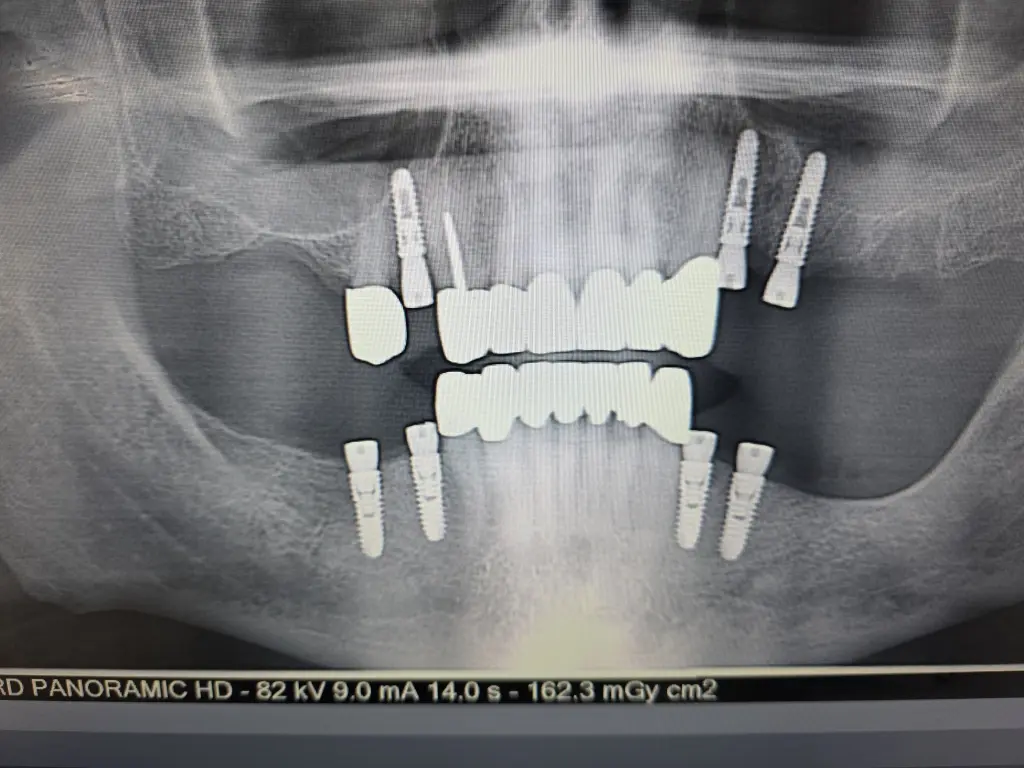

Fulll Mouth

Implants london

Single Jaw

from £12,000

Full Mouth Implants

from £22,000

All Inclusive:

Surgery

Implants

IV Sedation

Zirconia Implant Bridges

5 Years Warranty